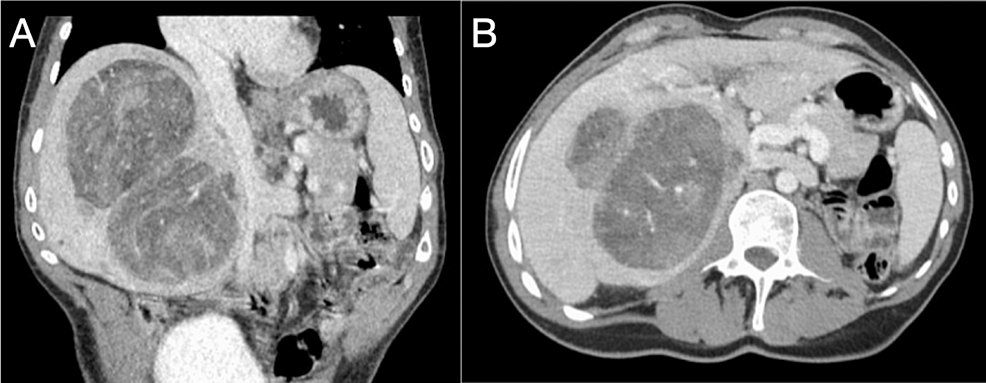

Liver Transplantation as a Treatment for Unresectable Hepatic Adenoma in a Patient With Abernethy Syndrome Monday, 20 May, 2024 Cureus